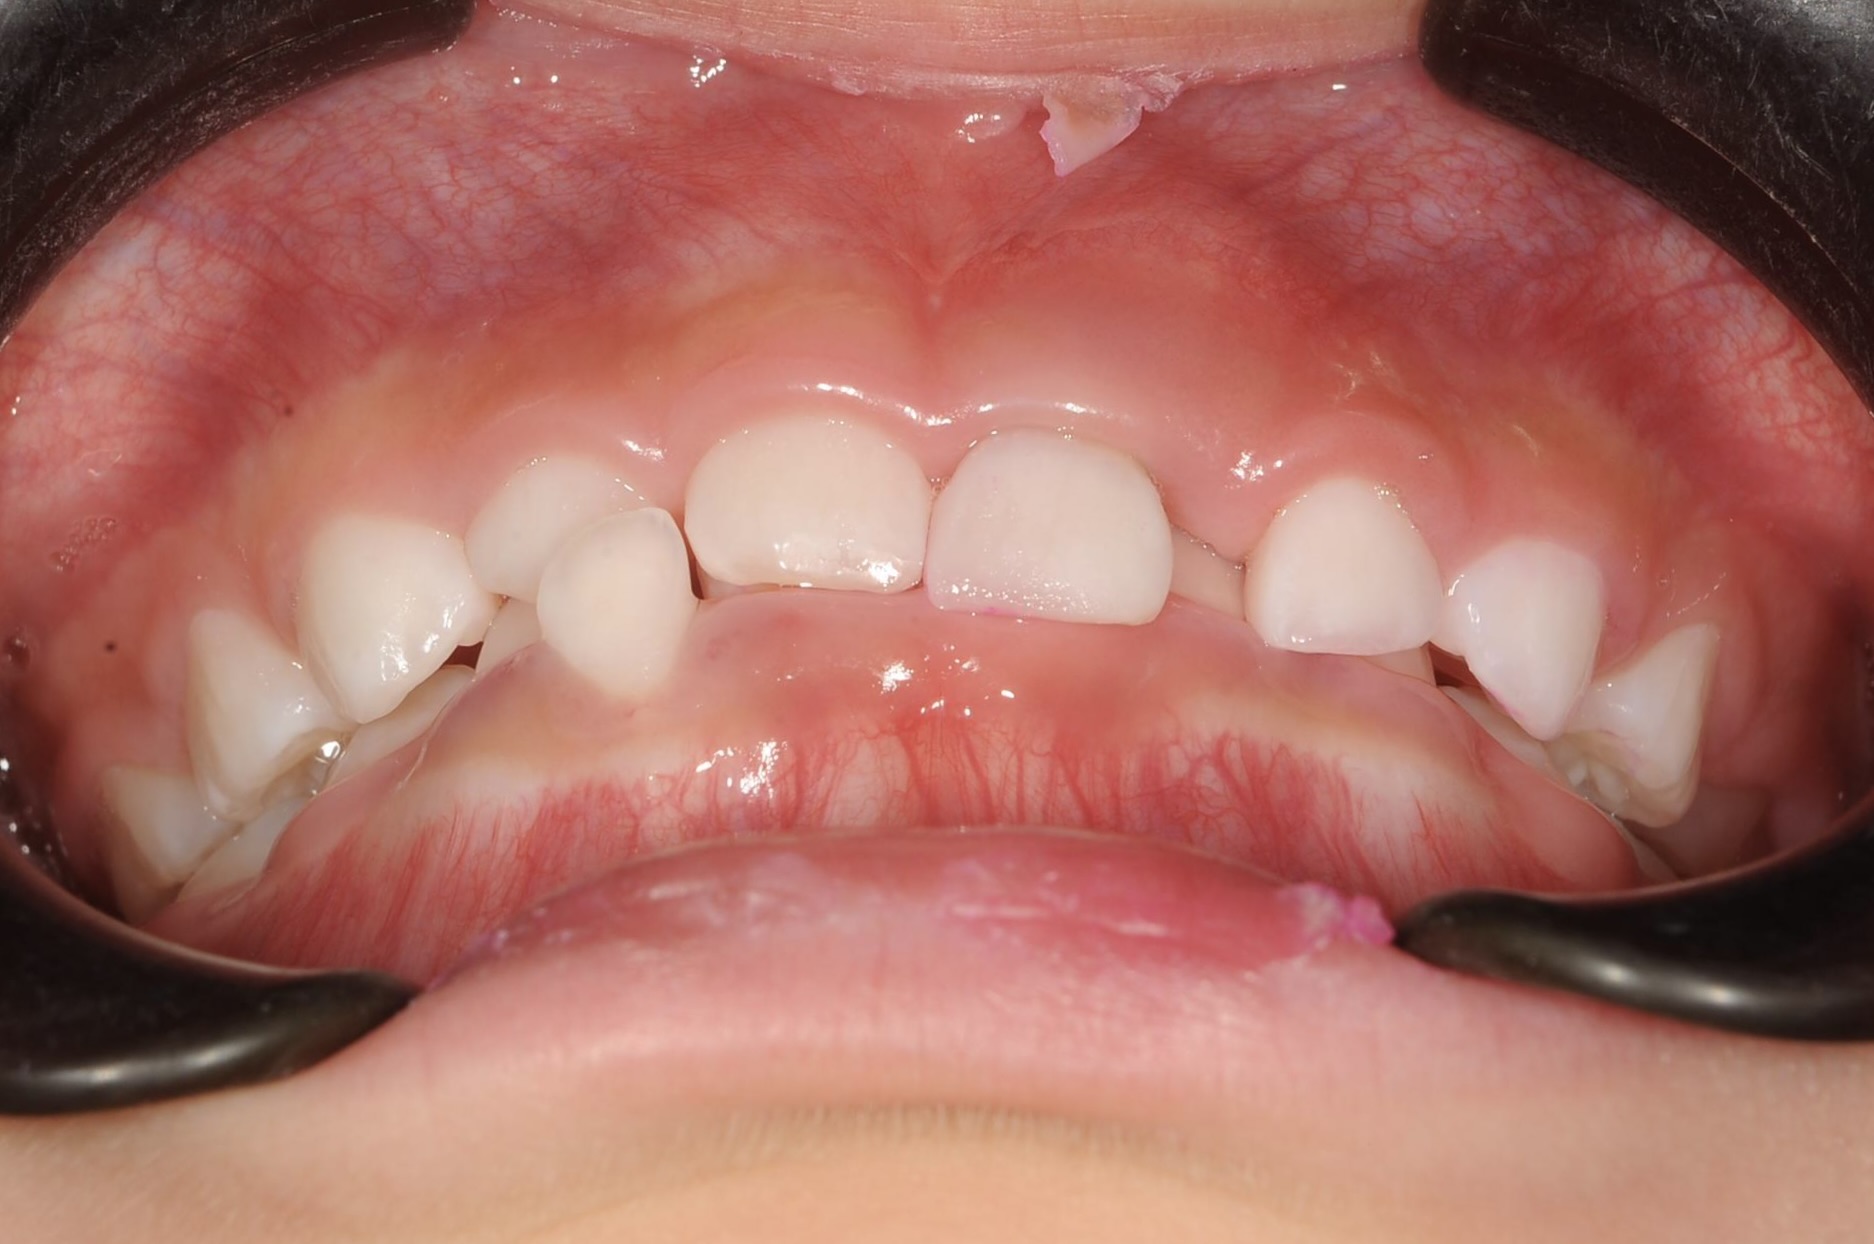

5歳 女児 小児矯正

歯並びの状態:

叢生(ガタガタ)

過蓋咬合(咬み合わせが深い)

BEFORE

主訴

右下の歯が飛び出ているので治したい。

診断名・主な症状

過蓋咬合

年齢

5歳

治療内容

上下の歯並びの幅を拡げつつ、前歯の関係を改善しました。